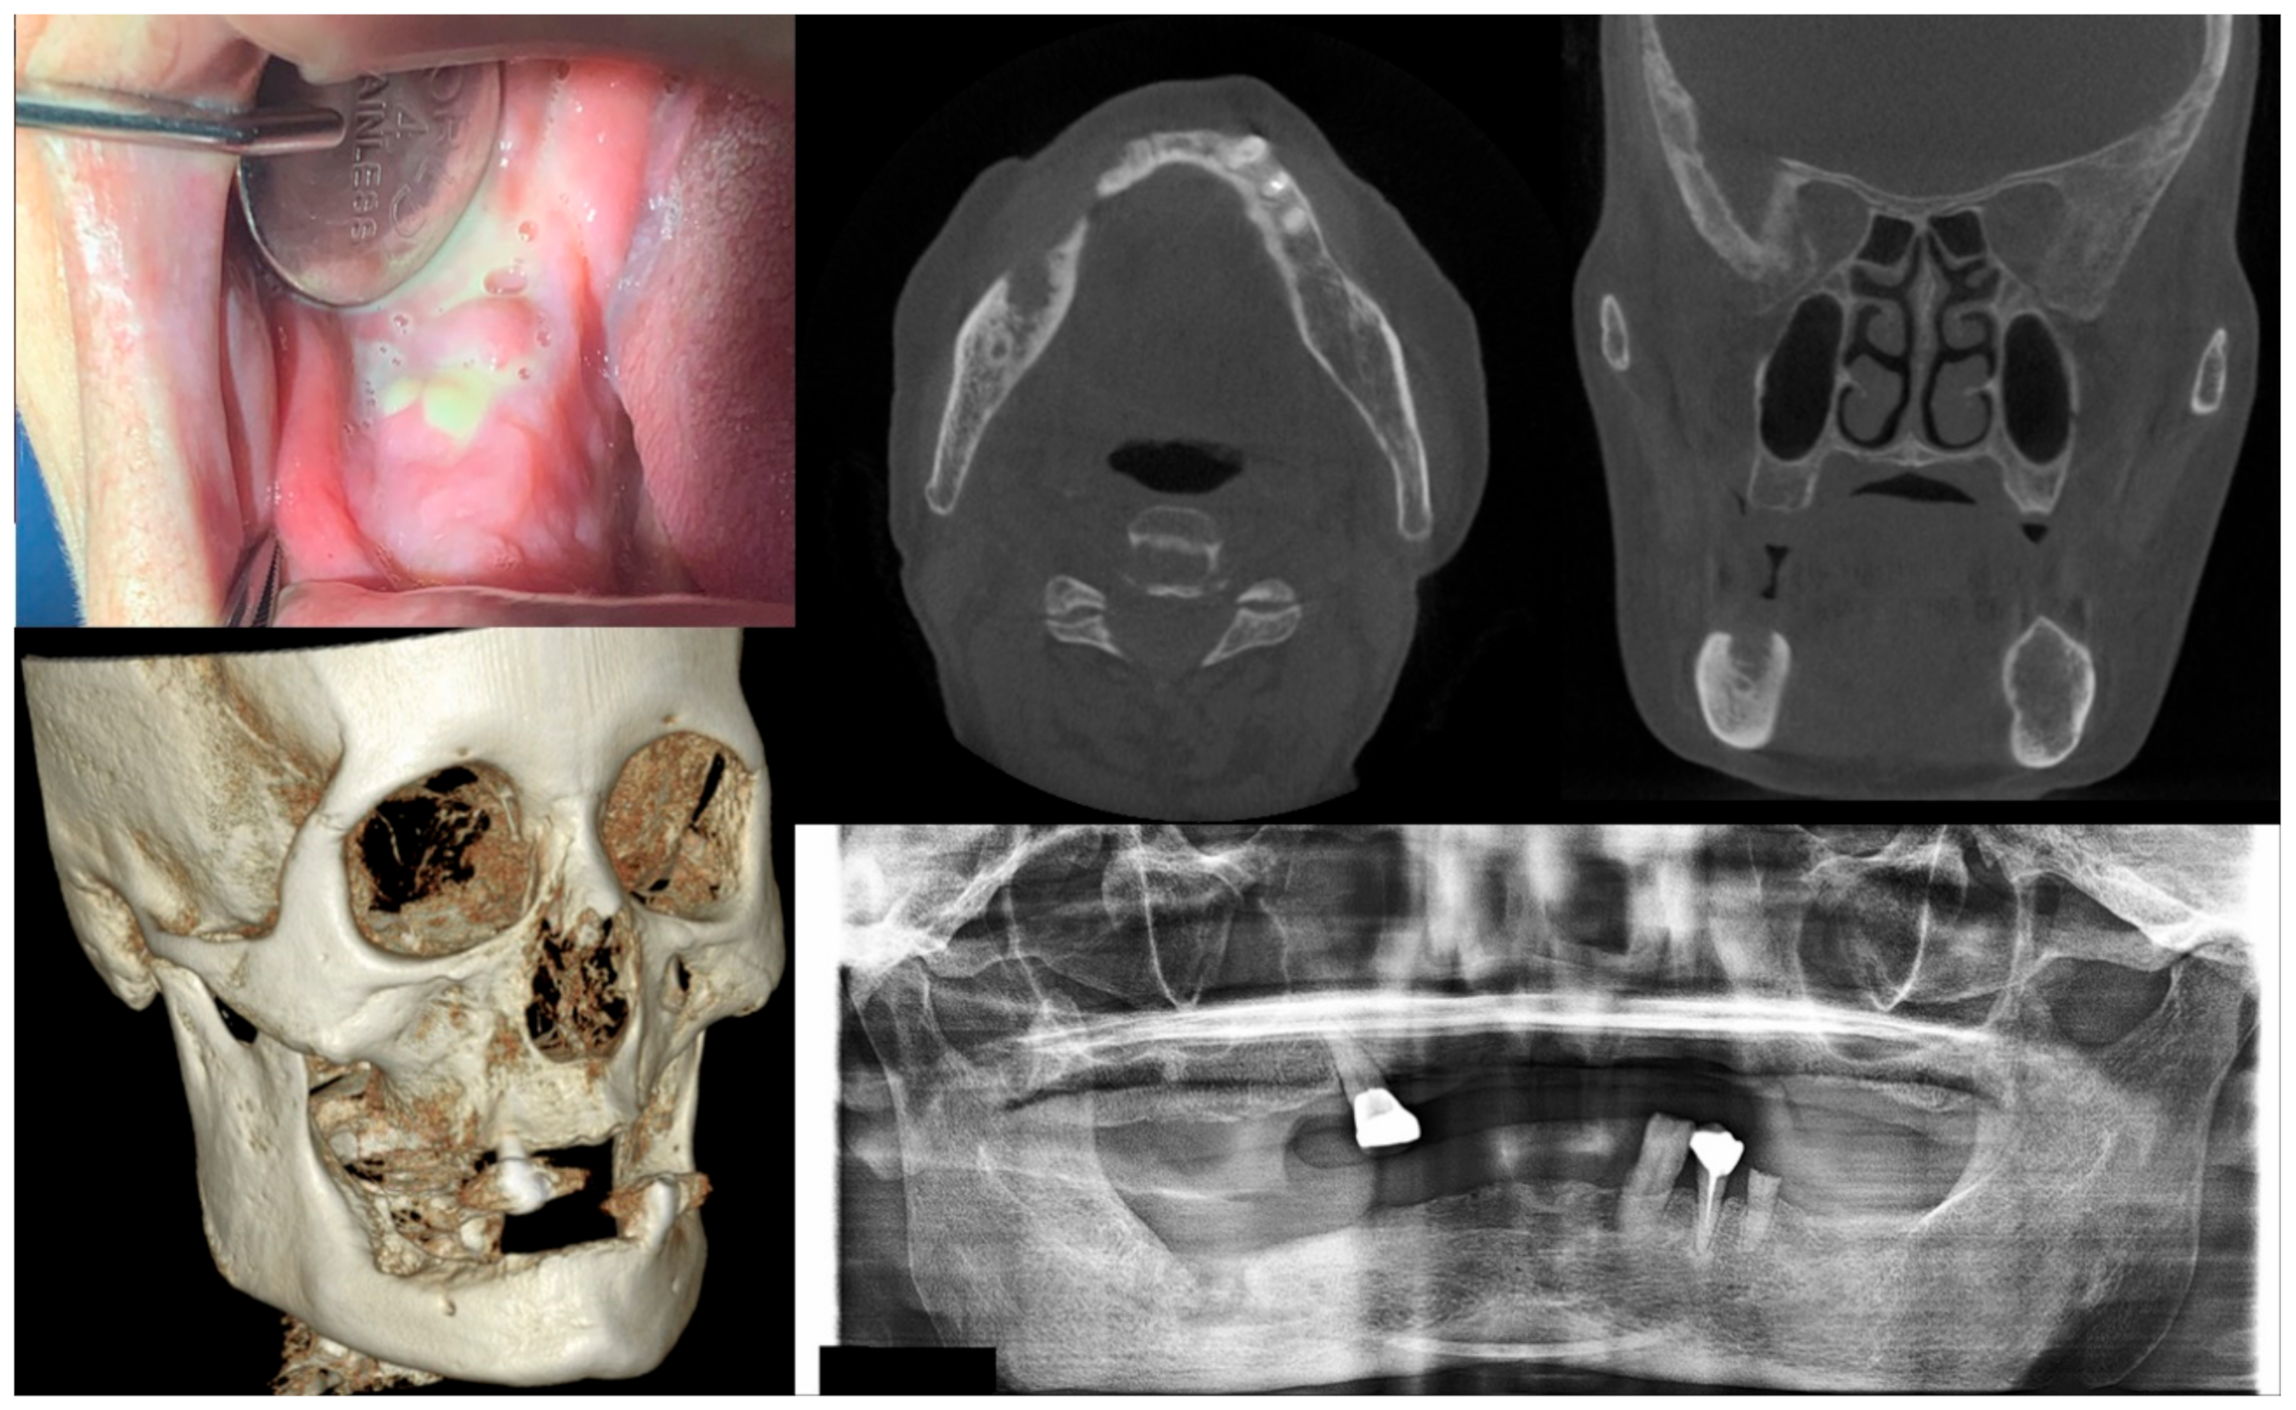

2.1. Staging of MRONJ and Treatment Strategies

| Stage | Clinical Manifestation | Strategies for Management |

|---|---|---|

| At risk | No apparent necrotic bone | Patient education, no treatment required |

| 0 | No clinically necrotic or exposed bone with nonspecific clinical and radiographic findings | Systemic medication, including antibiotics and pain-killers when indicated |

| 1 | Exposed necrotic bone or intraoral fistula with no symptoms and no infection | Patient education, oral antibacterial rinse, close clinical follow-up |

| 2 | Exposed necrotic bone or intraoral fistula showing symptoms and signs associated with infection | Antibacterial oral rinse, systemic medication with antibiotics and pain-killers, debridement reducing the volume of necrotic bone for infection control |

| 3 | Exposed necrotic bone or intraoral fistula showing symptoms and signs associated with infection + exposed necrotic bone invading the inferior border of the mandible or the sinus floor of the maxilla and/or extraoral fistula and/or oroantral fistula | Antibacterial oral rinse, medication with antibiotics and pain-killers, surgical treatment including open debridement/resection for long-term control of symptoms and infection |